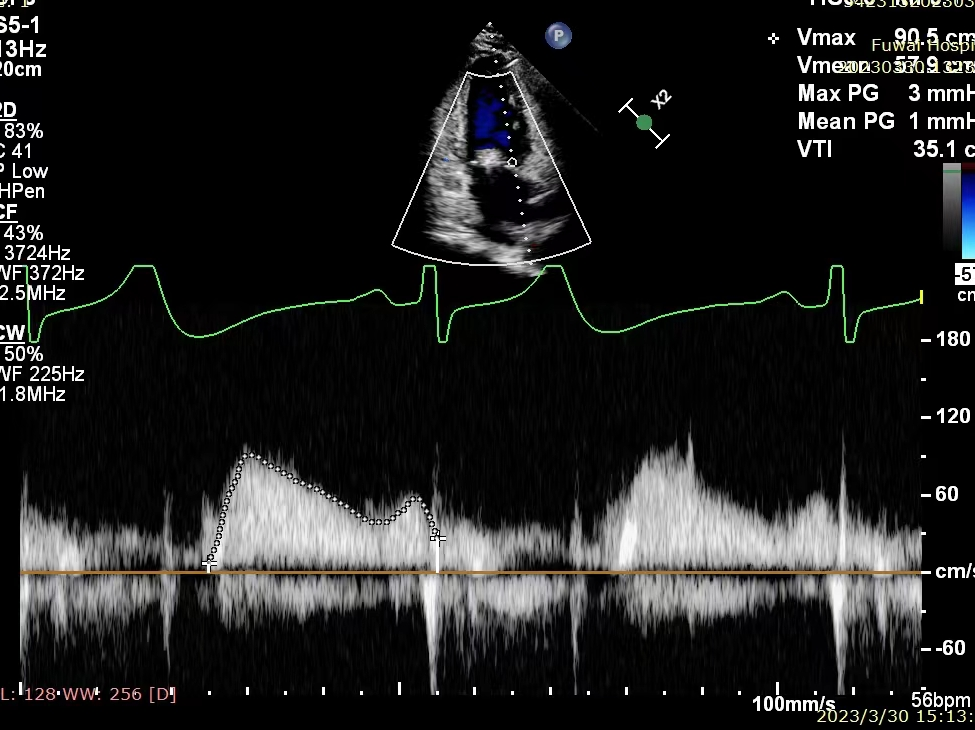

释放MitraClip™,超声显示反流降至微量,平均跨瓣压差3mmHg, 患者各项生理指标正常,手术顺利完成

术后即刻超声图